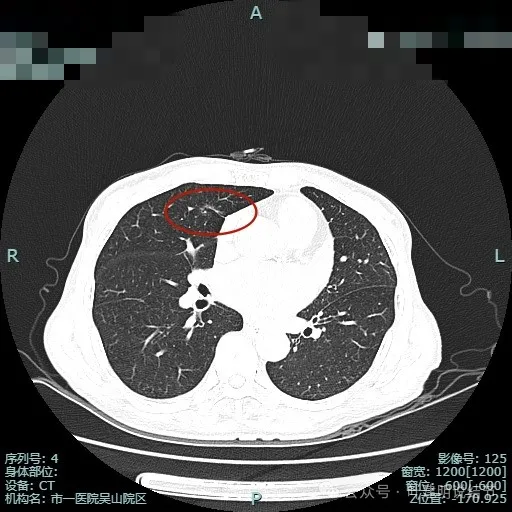

先来看2024年6月某省级医院的影像:‘

这个病灶是混合密度,边缘毛糙有细毛刺,毛刺较锐利,灶内有细支气管通气征,整体轮廓较清。如果之前也有在的,则基本上肯定是肺癌,而且至少是微浸润性腺癌。